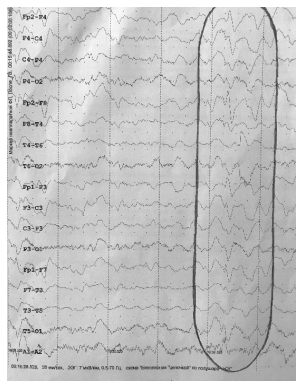

Повышен уровень трансаминаз в биохимическом анализе крови (АЛТ — 110 Ед / л, АСТ — 136 Ед / л). Стенозирующее поражение брахиоцефальных сосудов — правой внутренней сонной артерии до 60%, левой общей сонной артерии — до 45%. На МСКТ мягких тканей шеи — липомы. ЭЭГ — основной ритм коры диффузно замедлен до 6–7 Гц, выраженные диффузные дизрегуляторные изменения биоэлектрической активности головного мозга; при проведении гипервентиляционной пробы на фоне диффузного нарастания индекса медленной активности тета- и дельта-диапазона появляются короткие диффузные разряды из медленных комплексов «острая-медленная волна», частотой 2 Гц, средней амплитуды 110 мкВ с акцентом в бифронтальных отведениях (рис. 4). ЭНМГ (стимуляционная, игольчатая): дельтовидная мышца — спонтанная активность в виде потенциалов фибрилляций (ПФ), положительных острых волн (ПОВ); mm. vastus lateralis — cпонтанная активность представлена ПФ, единичными ПОВ; mm. trapezius — спонтанная активность в виде ПФ, ПОВ, единичного псевдомиотонического разряда; признаки аксонального поражения сенсорных волокон срединных и локтевых нервов (сенсорная полиневропатия); грубая сенсорно-моторная полиневропатии нижних конечностей; уменьшение средних величин длительности потенциалов двигательных единиц (ПДЕ) и амплитуды отдельных потенциалов на фоне спонтанной активности с дельтовидных и трапецевидных мышц, что свидетельствует о текущем первично-мышечном заболевании и соответствует ЭМГ-картине, наблюдаемой при миопатии; ответы с передних большеберцовых и латеральных головок четырехглавых мышц бедер указывают на невральный тип поражения. Отмечено, что во время проведения исследования у пациента при его переходе из горизонтального положения в вертикальное развился приступ общей слабости с тахикардией, одышкой, гипергидрозом, что свидетельствовало о периферической вегетативной недостаточности.

Рис. 4. ЭЭГ — при проведении гипервентиляционной пробы на фоне диффузного нарастания индекса медленной активности тета- и дельта-диапазона появляются короткие диффузные разряды из медленных комплексов «острая-медленная волна», частотой 2 Гц, средней амплитуды 110 мкВ, с акцентом в бифронтальных отведениях.